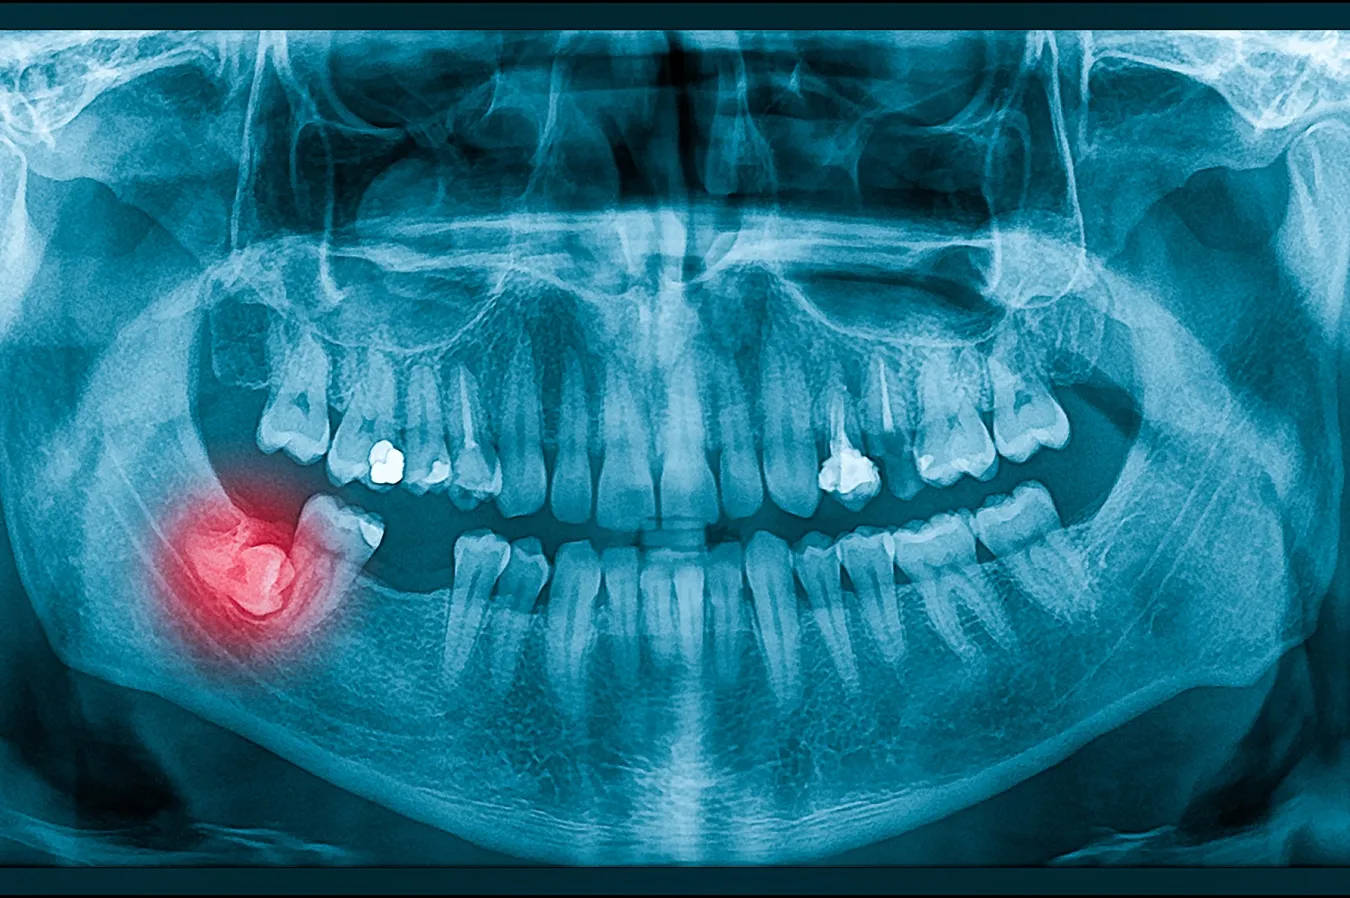

Wisdom teeth, also known as third molars, typically emerge between the ages of 17 and 25. For many people, these late-arriving teeth can cause more harm than good. At South Mississippi Oral Surgery & Implant Center, our experienced surgeons specialize in the safe, effective removal of wisdom teeth to protect your long-term oral health.

While some patients have enough space for their wisdom teeth to come in normally, most experience issues that make removal necessary. Common problems include:

- Impaction: Wisdom teeth often grow in at an angle or remain trapped under the gumline.

- Crowding: Even if they partially erupt, wisdom teeth can push against surrounding teeth, causing misalignment.

- Infection and Decay: Their location makes them hard to clean, increasing the risk of cavities and gum disease.

- Cysts and Damage to Nearby Teeth: In some cases, impacted wisdom teeth can lead to cysts or damage the roots of neighboring teeth.

Removing these teeth early, typically in the late teens or early twenties, can help you avoid pain, infection, and more complex dental issues down the road.

- Comprehensive Evaluation: We’ll use advanced digital X-rays or CBCT 3D imaging to assess the position of your wisdom teeth and plan your surgery.